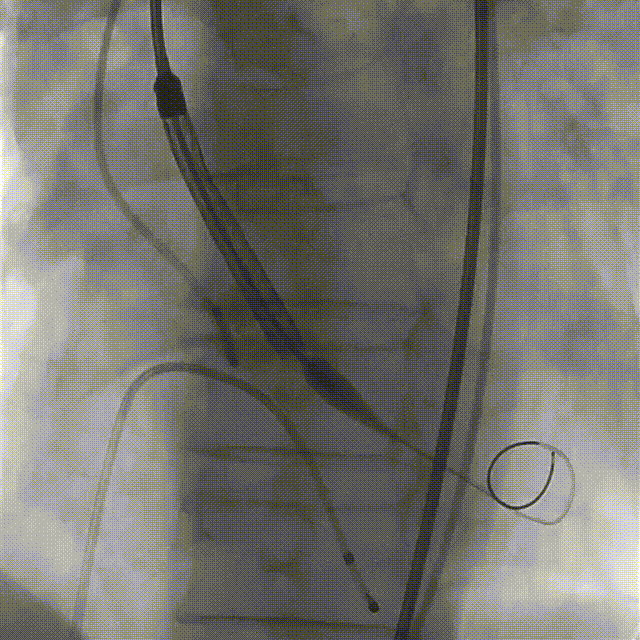

导丝跨瓣

导丝跨瓣极其困难,因其Type0型二叶瓣的独特结构,加之不均匀的钙化分布,引起瓣膜的贴合不良,难以找到准确的瓣口,多次弹出,最后成功过瓣后显示路径有明显弯度。